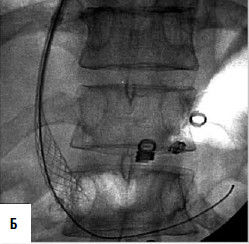

Рис. 84. Схема и рентгенограмма перитонеовенозного шунта при асците